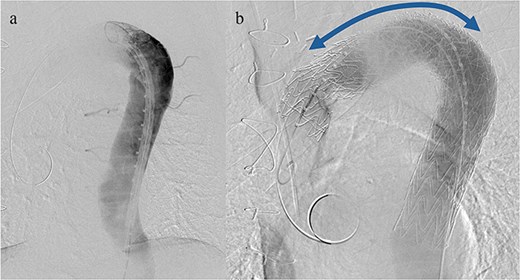

Given the ongoing hemoptysis, presumed aneurysmal expansion due to an occult endoleak, and the absence of any other obvious causes of hemoptysis, we determined that intervention for the aneurysm was necessary. TEVAR was performed using a right femoral artery approach. Initial angiography did not reveal contrast leakage into the sac (Fig. 3a). A 34 × 34 × 200 mm Gore Conformable TAG stent graft (W.L. Gore & Associates, Flagstaff, AZ, USA) was deployed to cover the distal edge of the FET. The second stent graft, a 34 × 34 × 150 mm Gore Conformable TAG stent graft, was deployed overlapping the first graft immediately after the left subclavian artery branch to cover the entire length of the FET (Fig. 3b). Considering the proximal migration, a type Ib endoleak was deemed the most likely cause. However, the possibility of a type III endoleak from the graft was also considered, so the stent graft was deployed to cover the entire area. The patient’s hemoptysis resolved completely postoperatively. A follow-up CT 2 years later showed a reduction in the aneurysm size from 56 to 44 mm (Fig. 4).

(a) Angiography performed from within the FET before deploying the stent graft showing no evidence of endoleak or aortobronchial fistula. (b) Angiography after stent graft placement. The bidirectional arrow shows the original extent of the FET insertion.